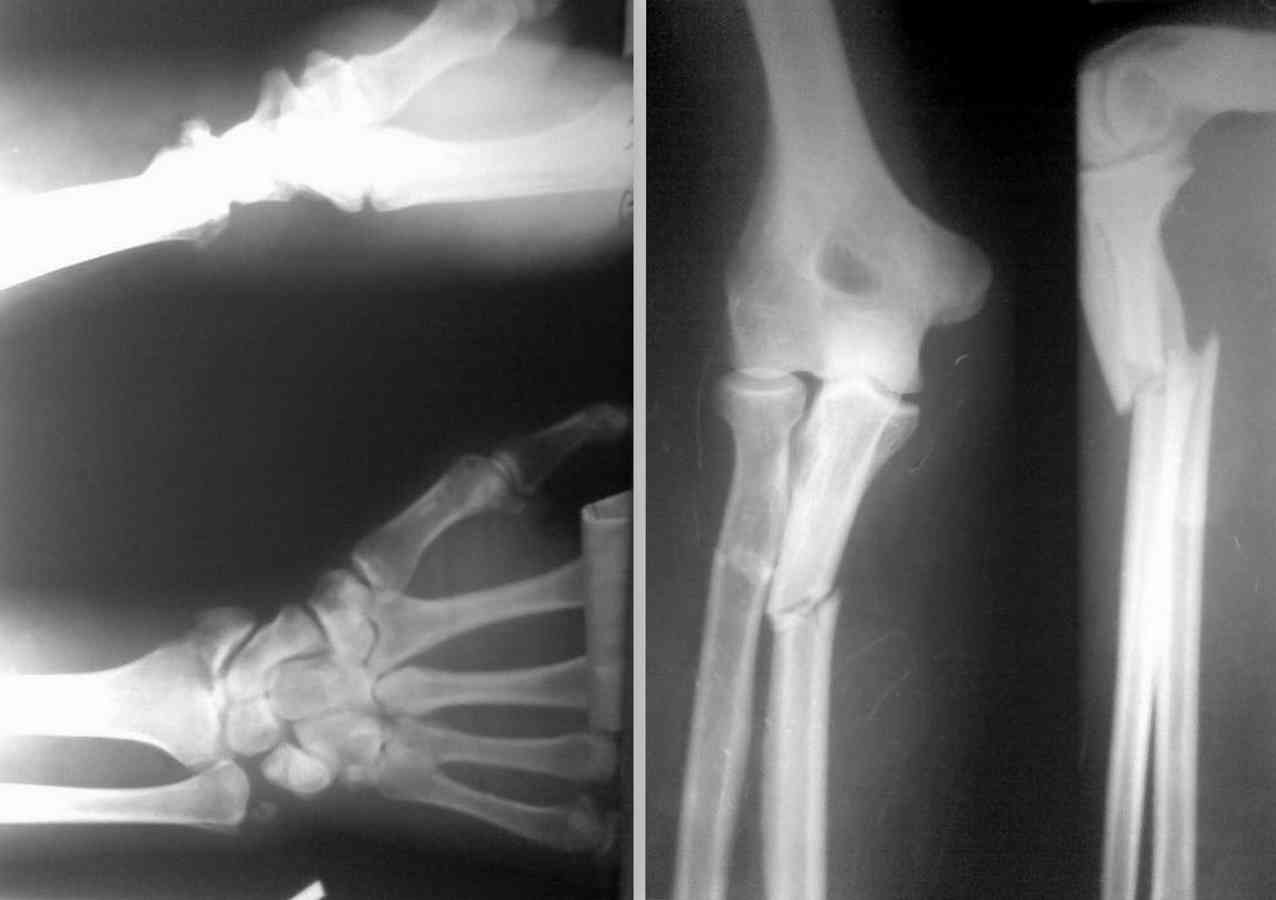

Добрый день,коллеги. Поступил больной 30 лет после падения с высоты 1,5 м.на ладонь. Травма 8 суток назад, в поле моего зрения попал только сегодня.

Неврологии нет. Со слов отмечался выраженный отёк предплечь,кисти и пальцев. В настоящее время отёк умеренный, движения пальцев кисти сохранены. Проблем с синтезом локтевой кости не вижу.

Имеются вопросы по лучевой, а именно:

1. Метод фиксации

2. порядок вмешательств

3. Необходимость фиксации дистального перелома луча

4. Предпочтительный доступ

Собственный план: Из тыльного доступа фиксировать проксимальный перелом луча пластиной типа LCP (короткий проксимальный фрагмент)Дистальный перелом фиксировать из тыльного(?) доступа винтом или может быть Ex-fix?